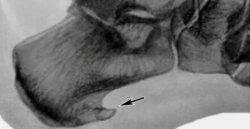

Диагностика заболеванияБоли при этом заболевании весьма характерны, поэтому выслушав жалобы пациента и прощупав стопу, специалист без труда ставит верный диагноз. Чтобы подтвердить диагноз и исключить другие заболевания делают рентгеновский снимок.

Кстати, сам по себе этот снимок без описания больным своих ощущений не является истиной в последней инстанции. Это объясняется тем, что у многих людей имеются анатомические шпоры, которые их никаким образом не беспокоят (это является их индивидуальной особенностью), и наоборот у людей, испытывающих сильные боли в области пятки на рентгеновском может быть не обнаружено никаких шпор.